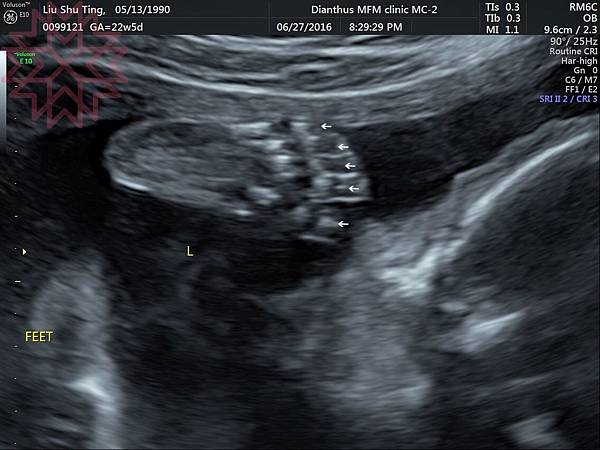

最後分享幾張玄學超音波照~

這就是讓我們數的很辛苦的腳ㄚ子~